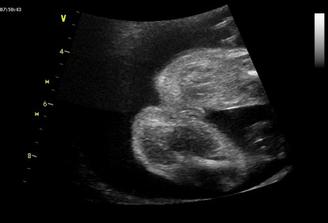

Tak se na nás snad už štěstí konečně usmálo a na IVF už nepůjdeme....... Měli jsme těsně před stimulkou na 2.IVF a čekali na mrchu. Místo toho jsme 15.3.2009 objevili naše krásné //. 17.03.2009 bylo na UTZ vidět plodové vejce, cca 2,7mm, další kontrola 31.3.2009. Tam už byl vidět náš bobeček, 6,3mm veliký a srdíčko mu bilo jako o závod. Dostali jsme krásné fotečky a jsme moc šťastní. Tak konečně je 23.4.2009 a jsme i s taťkou na dalším UTZ, jsme 9+6. Paní doktorka z nás měla velkou radost, říkala, že tak mrskající se miminko už dlouho neviděla. Velikostí odpovídáme úplně na den, máme už těhu průkajdu a dneska jsem se objednala na časný genet. skr. k MUDr. Břešťákovi. Termín porodu je 20.11.2009 a manža má narozky 24.11. 2009. No a já je mám zítra, takže super dnešní dárek. Tak dneska 11.5. 2009 jsem byla u zubaře pro razítko do těhu průkajdy a už ho mám. Další den 12.5.2009 jsme byli u mé praktické paní doktorky, natočila mi EKG a dala nám razítko do těhu průkajdy. Dneska 14.5.2009 jsme byli s manžílkem na genetickém screeningu. Pan doktor a sestřička byli moc hodní. Sestřička mi nabrala krev, vůbec jsem nezaznamenala, že je po odběru, je moc šikovná. Výsledky budou do 14-ti dnů. Pan doktor nám ukázal miminko v celé své kráse, jsme obříci, máme skoro 8 cm, NT 1,8 mm. Dle pana doktora jsme o 6 dnů větší a odpovídáme 13+5 (dle MS 12+6), tak nám upravil termín porodu na 14.11.2009. Slyšeli jsme tlukot srdíčka a bylo to nádherné, 160 úderů /min.. Pan doktor nám dal fotečky na CD, tak jsme moc šťastní. Jelikož nám pan doktor posunul termín porodu o týden dříve, tak jsme se byli 19.05.2009 zaregistrovat k porodu do FN Motol. Dneska 21.05.2009 jsme byli na kontrole a dostali jsme fotečky obličejíčka našeho mimíska. Je to celý tatínek. Mimísek na nás koukal a pěkně skotačil, paní doktorka nám ukázala jak má právě nožičku u hlavičky. Na den dětí 01.06.2009 jsme se dozvěděli, že výsledky screeningu jsou v pořádku. Jsme moc rádi. Dne 04.06.2009 jsem si volala na výsledky krevních triple testů a sestřička mi sdělila, že jsou v pořádku. Jsme s taťkou moc šťastní. Tak dneska 11.06.2009 jsme byli na kontrole u naší paní doktorky a s taťkou jsme byli zvědaví, jestli se nám už ukáže holčička nebo chlapeček. Paní doktorka se moc snažila, říkala, že by to viděla na holčičku, ale že opravdu spíše tipuje, protože miminko nechtělo roztáhnout nožičky. Tak uvidíme, jestli nám to řekne pan doktor na velkém UTZ, kam se objednáme. Bylo vidět, jak si miminko podpírá ručičkou bradičku a paní doktroka nám udělala nějaké fotečky. Jsme s tatínkem moc rádi, že se má miminko fajn. Dneska končíme 4. měsíc. Po měsíci -7.7.2009 jsme konečně zase viděli naše miminko. Paní doktorka nám ukázala močový měchýř, srdíčko, žaludek. Miminko se mrskalo, dokonce nám zamávalo. Paní doktorka nám řekla, že na 90% čekáme holčičku!

14.7.2009 jsme byli s taťkou na velkém UTZ (22+3) u pana MUDr. Břešťáka. Pan doktor byl fajn, ukázal nám miminka srdíčko, frekvenci srdíčka, tok krve do srdíčka a do aorty, játra, ledviny, močový měchýř..., dokonce i základy zoubků. Změřil všechny orgány a tělíčko a byl moc spokojený, vše je tak, jak má být. Nakonec nám potvrdil, že čekáme HOLČIČKU! Mrskala s sebou , chvíli trvalo, než pan doktor mohl změřit srdeční frekvenci. Vážíme 492g. Jsme s tatínkem moc šťastní, že je malá v pořádku. Dneska objednáme kočárek casualplay s4. Tak dneska 26.7.2009 jsme se byli s tatínkem podívat na naši holčičku na 4D UTZ. Udělali nám dvd a fotečku. Malá se nejdřív moc nechtěla ukazovat, schovávala se a točila se k nám zády. Pak si ale dala říct a krásně se nám ukázala. Je moc hezká, je to celý tatínek. Má jeho nosánek, pusinku, bradičku. Byla to sranda, zívla si a dala si nožičku k pusince, pak se pošťourala v oušku. A je to malá čertice, mrskala s sebou pěkně. Když jsme si jí doma prohlíželi na dvd, tak taťkovi dala pořádný kopanec, až vyskočil. 4D UTZ je fajn a my jsme spokojení. 4.8.2009 jsem byla na testu na cukrovce, ble. Ale nebylo to tak hrozný a máme splněno. 5.8.2009 jsme volali na vysledky jak nám cukrovka dopadla a výsledky jsou v pořádku, jupíí. Hnedka jsem to oslavila 2x koblihou a 2x croisantem. 11.8.2009 jsme byli na kontrole, malinká je v pořádku a je otočená hlavičkou dolů. Paní doktorka říkala, že je šikovná a že si myslí, že už takhle zůstane. Tak konečně uběhl měsíc a kousek a my se jdeme s taťkou podívat na naši holčičku. Paní doktorka říkala, že bude Michalku měřit, jsme totiž 32. týden. Paní doktorka malou změřila, odpovídáme úplně na den 31+3 a vážíme 1445g. Paní doktorka říkala, že Michalka je krásně proporční miminko, úplně podle tabulek a že by měla při porodu mít okolo 3500g. Michalka je moc šikovná, je stále hlavičkou dolů. Jupííí, jsme s tatínkem moc rádi. 01.10.2009 jsme byli u paní doktorky na další kontrole a Michalka se má dobře, krásně jí tlouklo srdíčko a je stále hlavičkou dolů, jupíí. Dostali jsme formulář na mateřskou a od 09.10.2009 na ní nastupujeme, jůůů, toto letí. Tak dneska je 13.10.2009 a byli jsme na poslední kontrole u naší paní doktorky, malá se má dobře, hlavičkou je stále dolů a váží 2300g, je to pěkný cvalík. Máme s tatínkem radost. CS máme 2. Už budeme chodit na kontroly do porodnici v Motole, kam se musíme objednat. 27.10.2009 jsem byla poprvé v poradně v Motole, paní doktorka nás vyšetřila, CS asi 4, pak jsme poslouchaly srdíčko naší malé princezny, zrovna cvičila spartakiádu. Kontrola v pořádku. Další kontrola bude i s monitorem, tak se moc těšíme. Dnes 03.11.2009 jsem byla v poradně v Motole, poprvé nám dělali monitor a malá se tak vrtěla, až mi sklouzla sonda a musela jsem si jí tam pak držet. Malá měla výsledky monitoru v pořádku, tak jsme moc s tatínkem rádi. Paní doktorka mě dnes nevyšetřovala, až zase na příští kontrole. Dneska je 10.11.2009, náš další den, kdy jsme se vydali do poradny. Natočili nám monitor, výsledky monitoru jsou v pořádku a paní doktorka mě i vyšetřila. CS 4, čípek zkrácený, měkký, hlavičkou je hezky nastavená. Je to naše malá šikulka a už se na ní s tatínkem móóc těšíme!!!